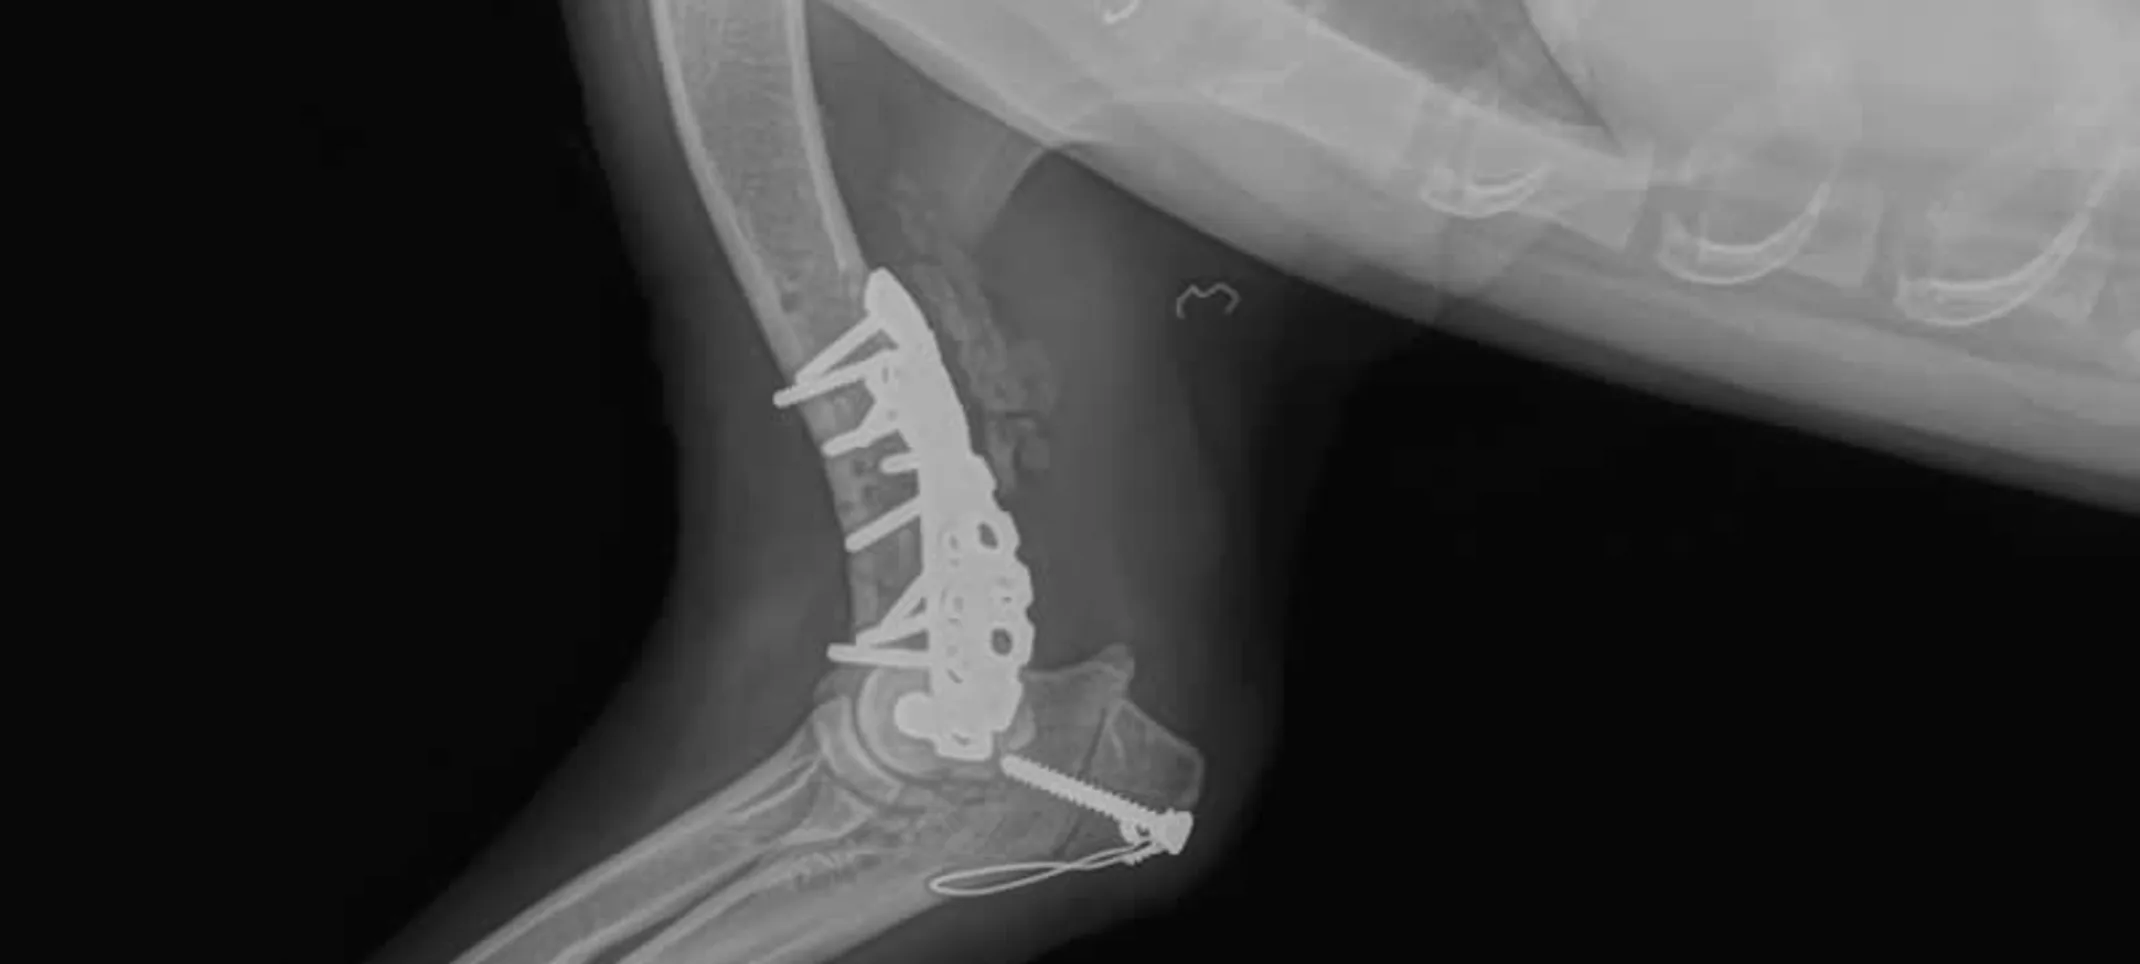

Bone plates are one of the strongest and most effective methods of fixing a fracture. This internal fixation technique counteracts bending, compression, twisting and pulling forces. The biggest advantage of bone plating is early return of function or use of fractured limb.

There are different types of plates and plating techniques, used for specific fractures. We commonly perform use of plates in compression, neutralization and bridging/buttress fashion depending on type of fracture and number of bone fragments. We have adopted the advanced “Locking” plate technique which works as internal fixators and allow for preservation of blood supply to the fractured bone. By preserving tissue integrity in the vicinity of the fracture, locking plates provide faster and stronger fracture healing.

We use also use Plate-Rod (combination of a bone plate and IM pin). They provide a very strong fixation of the bone, and allow use of the leg almost immediately after the surgery. Micro motion from that the stresses placed on fractured bones actually hasten healing, so if the pet is able to bear weight on the fractured leg as soon as possible, it is gaining strength in that leg and it will heal much faster than an animal who is not bearing weight on their injured leg.